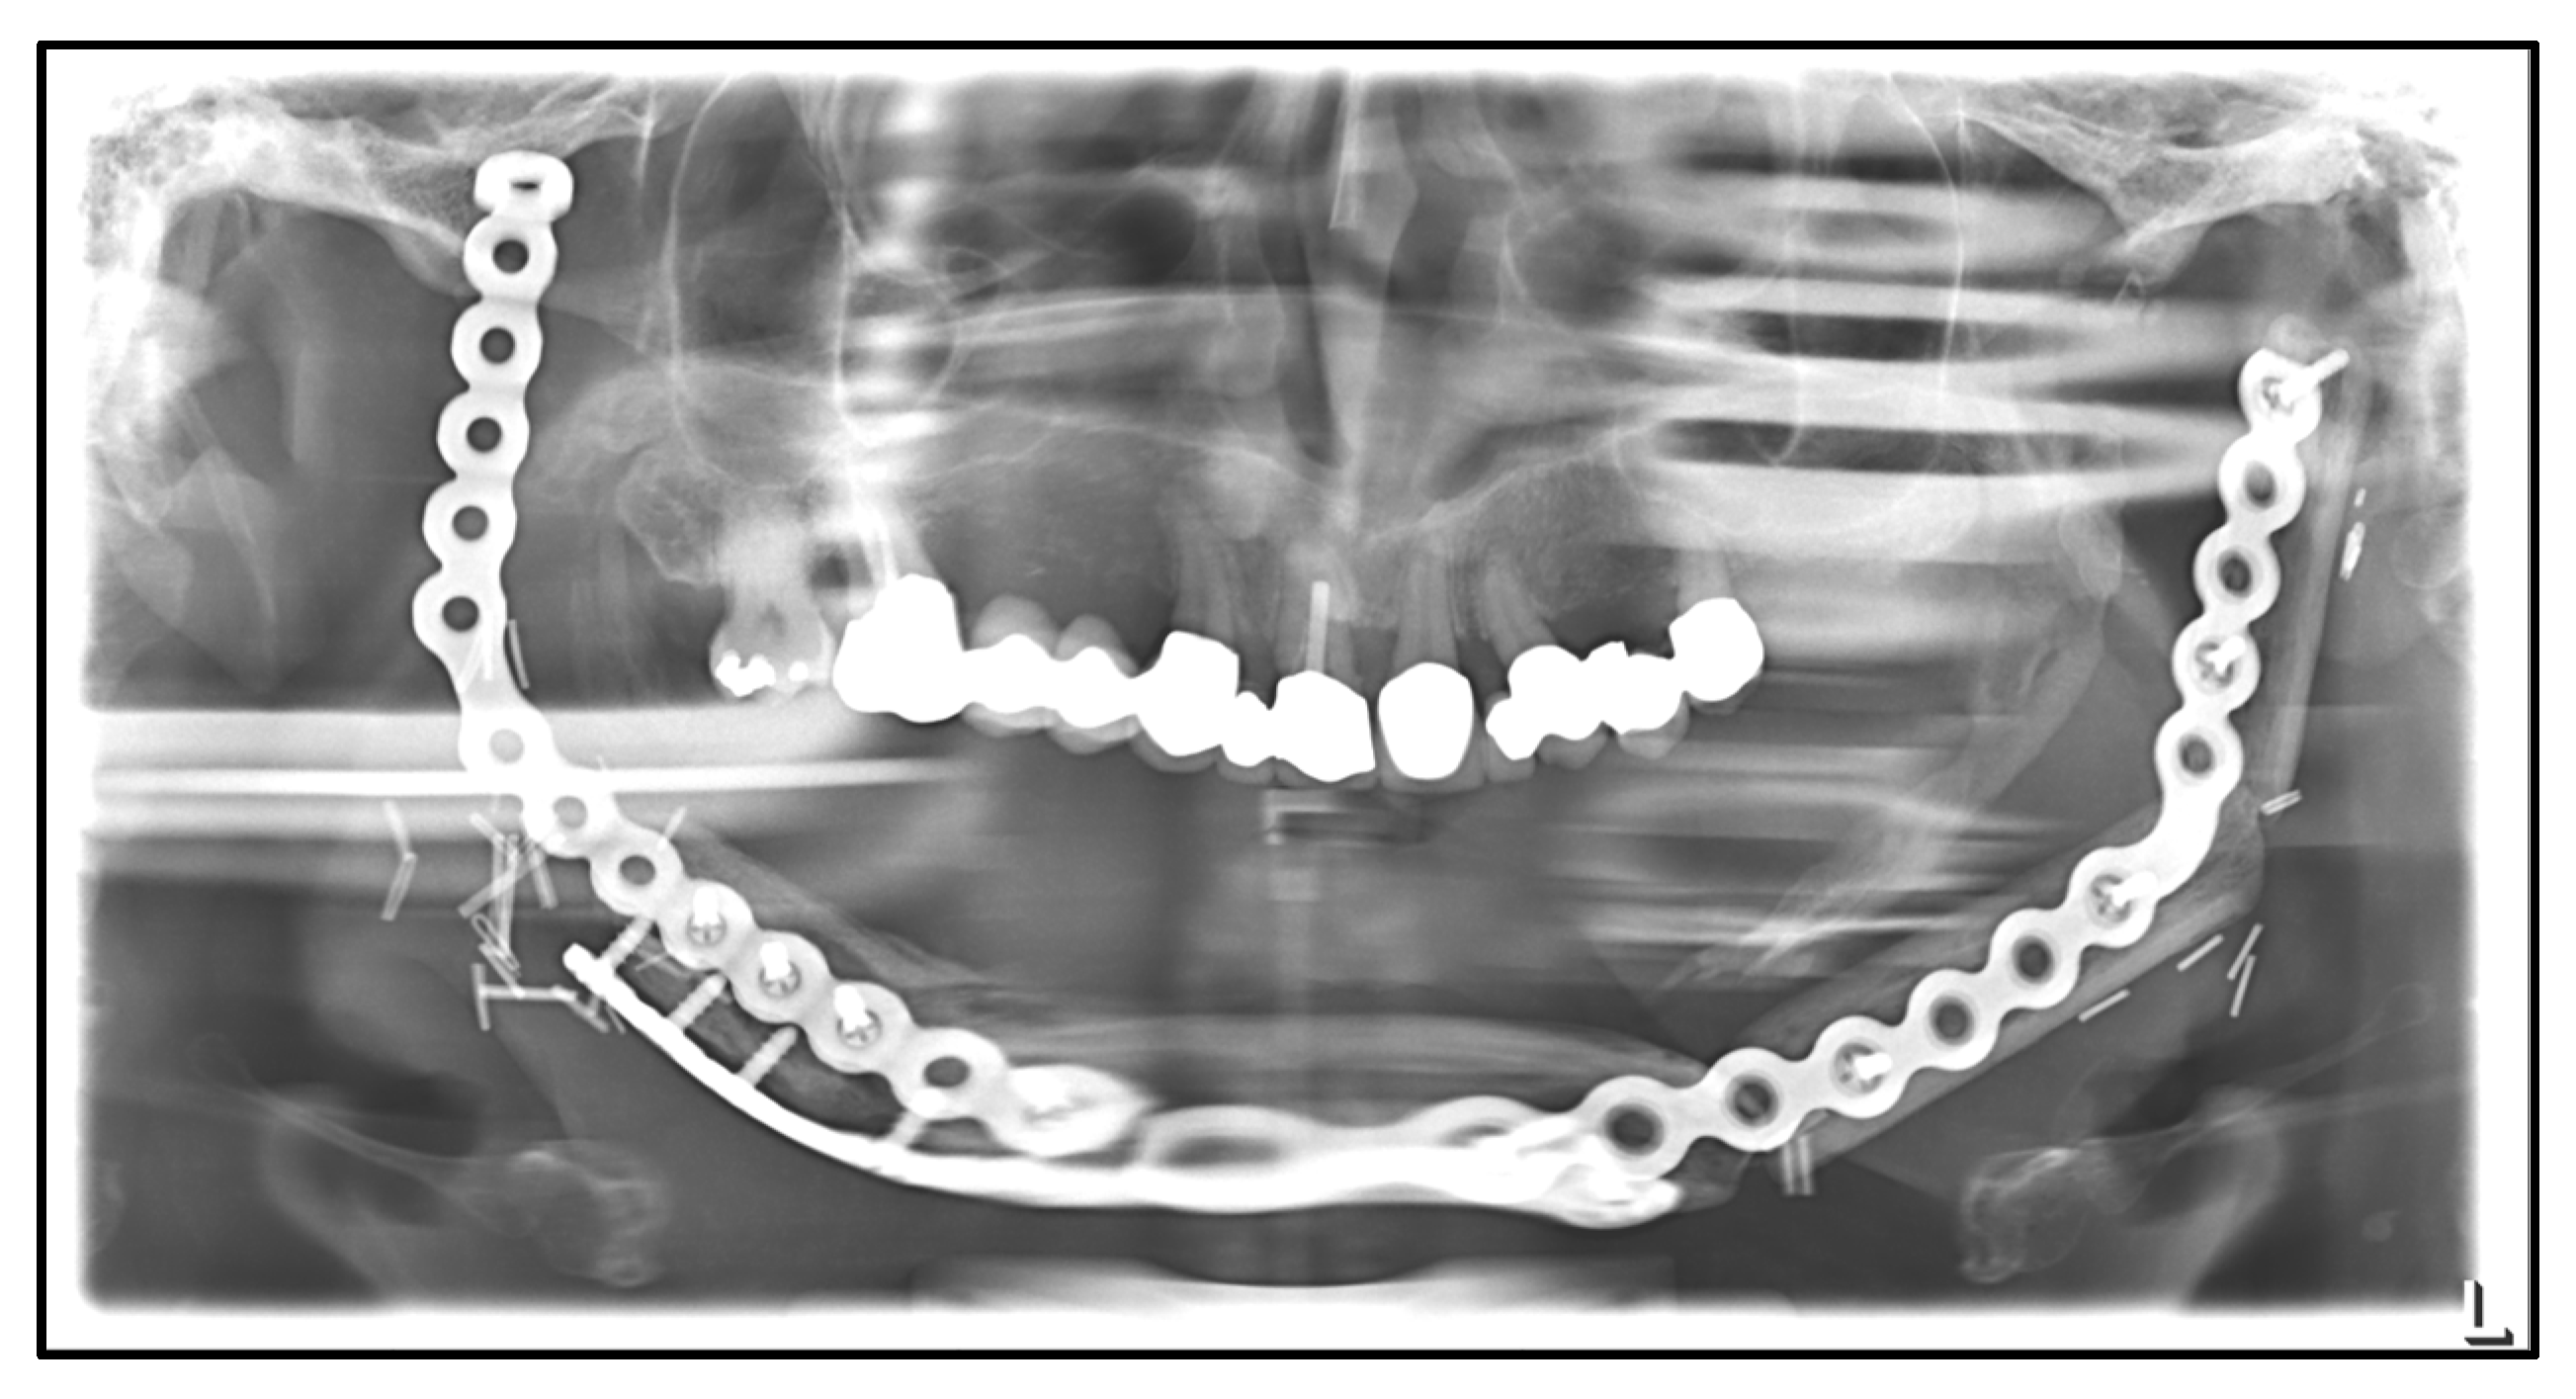

| September 2022: | Partial mandibular resection from the left mandibular angle to the right mandible, including the right temporomandibular joint, CAD/CAM-guided reconstruction with a bilateral free scapula flap with skin island, and patient-specific plate. In the course: